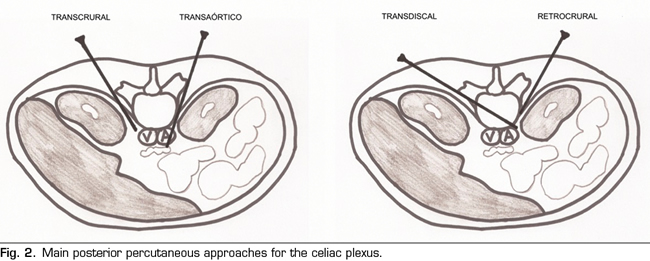

Once this issue is clarified, we can classify percutaneous approaches as follows (Figure 2):

Transcrural approach: the most commonly used for the blockage of the celiac plexus (Figure 3). The patient is placed in prone position, identifying the vertebral body L1 and advancing a needle on each side, approximately 7.5 cm from the midline, until it crosses the diaphragmatic crura and blocks the plexus.

Retrocrural approach: an approach that has been classically described for both the celiac plexus block (at the L1 level) and for the splanchnic nerves. In the pure retrocrural approach, the patient is placed in prone position and the vertebral bodies of T11 and T12 are located, advancing the needles to the anterior third of these bodies and thus blocking the splanchnic nerves.

Transaortic approach: described by Ischia et al. (14), it is a unilateral approach with the patient in prone position, accessing from the left side of the vertebral body of L1 until crossing the aorta and leaving the tip of the needle anterior to it. Blood output will be appreciated at the moment in which we cross the artery, with a posterior cessation as soon as we are anterior to it. It has been found that the risk of occult bleeding is low since in this area the aorta is reinforced by diaphragmatic crura and prevertebral fascia. However, publications are scarce and studies of larger scientific evidence are needed. Specific contraindications for this approach are the presence of abdominal aortic aneurysm, mural thrombosis and calcifications.

Transdiscal approach: it is performed under CT monitoring through the intervertebral disc T12-L1 until reaching the splanchnic nerves. Although the literature is scarce, this approach theoretically reduces the risk of complications such as paraplegia, pneumothorax and liver or kidney perforation, since the needle is inserted closer to the midline, being very useful in patients with anatomical abnormalities around of the celiac plexus or in patients with organomegalies (15,16).

Abdominal approach: normally used under ultrasound vision by anterior route.